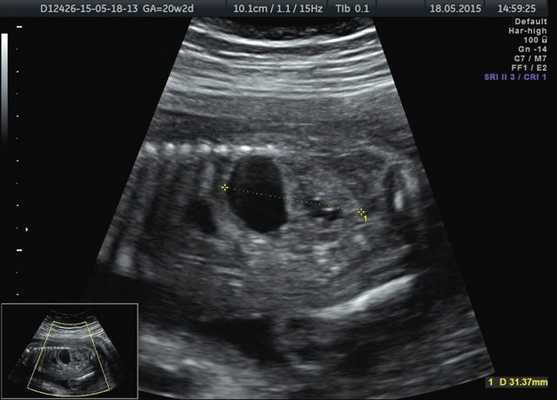

Левая почка была увеличена до 31×19×25 мм, преимущественно за счет анэхогенного образования с однородным содержимым до 16 мм в диаметре. Образование исходило из верхнего полюса почки и располагалось под ее капсулой. Сама почка была смещена книзу. При этом лоханка была незначительно расширена - до 4 мм, в то время как чашечки расширены не были. Левый мочеточник не визуализировался (рис. 3).

Рис. 3. Кистозное образование у верхнего полюса левой почки плода.